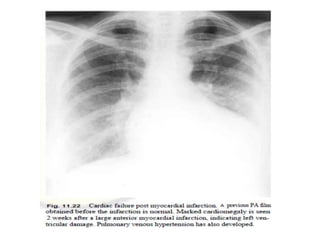

• Also includes progressive enlargement of the

heart, more often identified in anterior MI

• If the serial films taken over the first few days

or weeks following MI: progressive cardiac

enlargement, an important adverse

prognostic sign that should be further

evaluated.